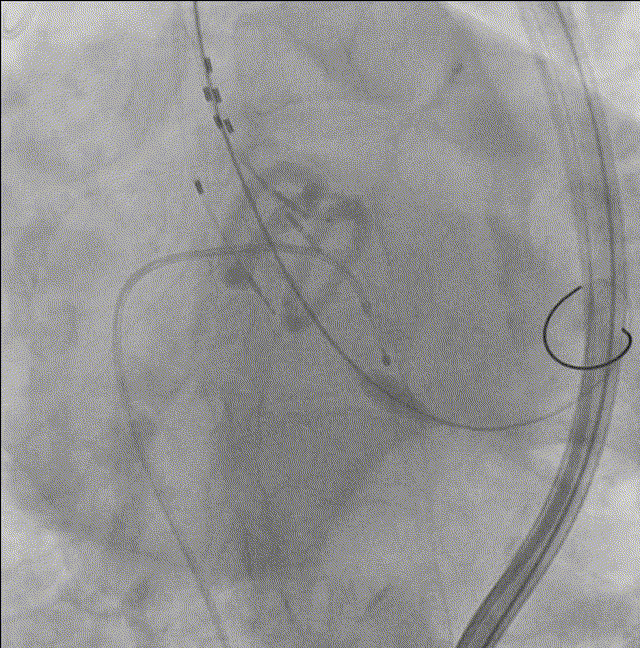

主动脉根部造影

5. AL2导管配合直头超滑导丝跨瓣;